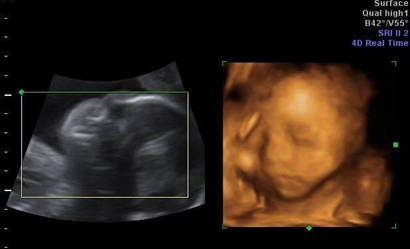

三:彩超单上很小英文字母Qual high 1是女孩,2是男孩。

四:通过四维彩超图看清胎儿性别,在六个月以后照四维彩超,只要宝宝的姿势是正面不是给个背影什么的,是男是女一看就知道。不过因为国家明文规定不能查胎儿性别,所以医生不会把能明显看出性别的一面照给妈妈看。